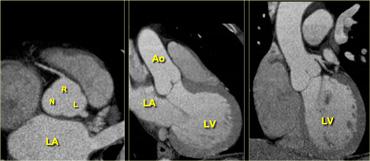

Tái tạo mặt cắt ngang (trái), mặt cắt 3 buồng (giữa) và tái tạo mặt cắt vành (phải) của tim minh họa mối tương quan giữa nhĩ trái, thất trái và gốc động mạch chủ. LA=nhĩ trái, R=lá vành phải, L=lá vành trái, N=lá không vành, Ao=động mạch chủ, LV=thất trái